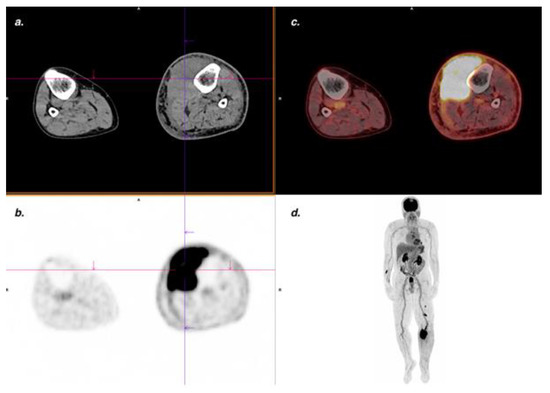

3.4. Overall DA on a Per-Lesion Basis

3.5. DA of FDG PET/CT for Cutaneous Lesions

| Muscle | 4 | 0 | 71 | 0 | 100% | 100% | 100% | 100% | 100% |